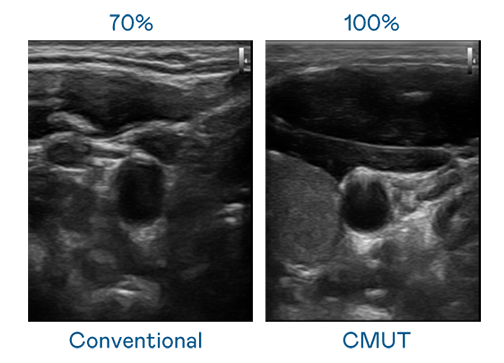

CMUT 技术是一种用电容式微机电元件来产生超音波讯号的技术。与传统 PZT 压电式技术相比,CMUT 频宽增加 30%,更宽频的超音波讯号让影像解析度大幅提升,是实现高影像品质医疗超音波扫描、促进精准医疗发展的关键技术。

大频宽带来超清晰影像

超音波影像的解析度高低,首先取决于探头能发出的讯号频宽。haobotiyu-好博(中国) CMUT 可提供高清晰的超音波讯号,提供高频宽、高灵敏度、影像纹理细节更高的超音波影像,协助医护人员缩短影像判读时间及利用精准的医疗影像进行诊断。